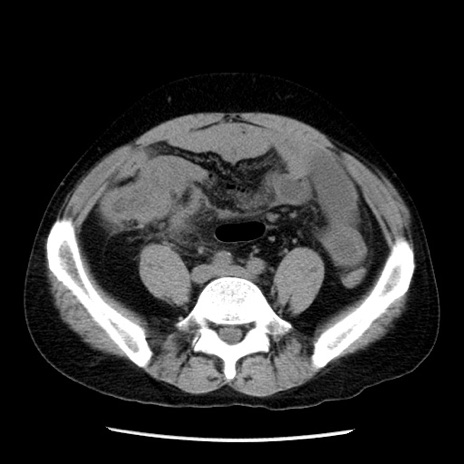

症例29(横断像)

【症例】40歳代男性

【現病歴】2日前から胃痛あり。徐々に周期的な激痛に変化した。本日になっても激痛があるため受診。

【身体所見】意識清明、BT 38-39℃台あり、腹部:膨満、やや硬、右下腹部に圧痛あり。

【データ】WBC 8500、CRP 23.26